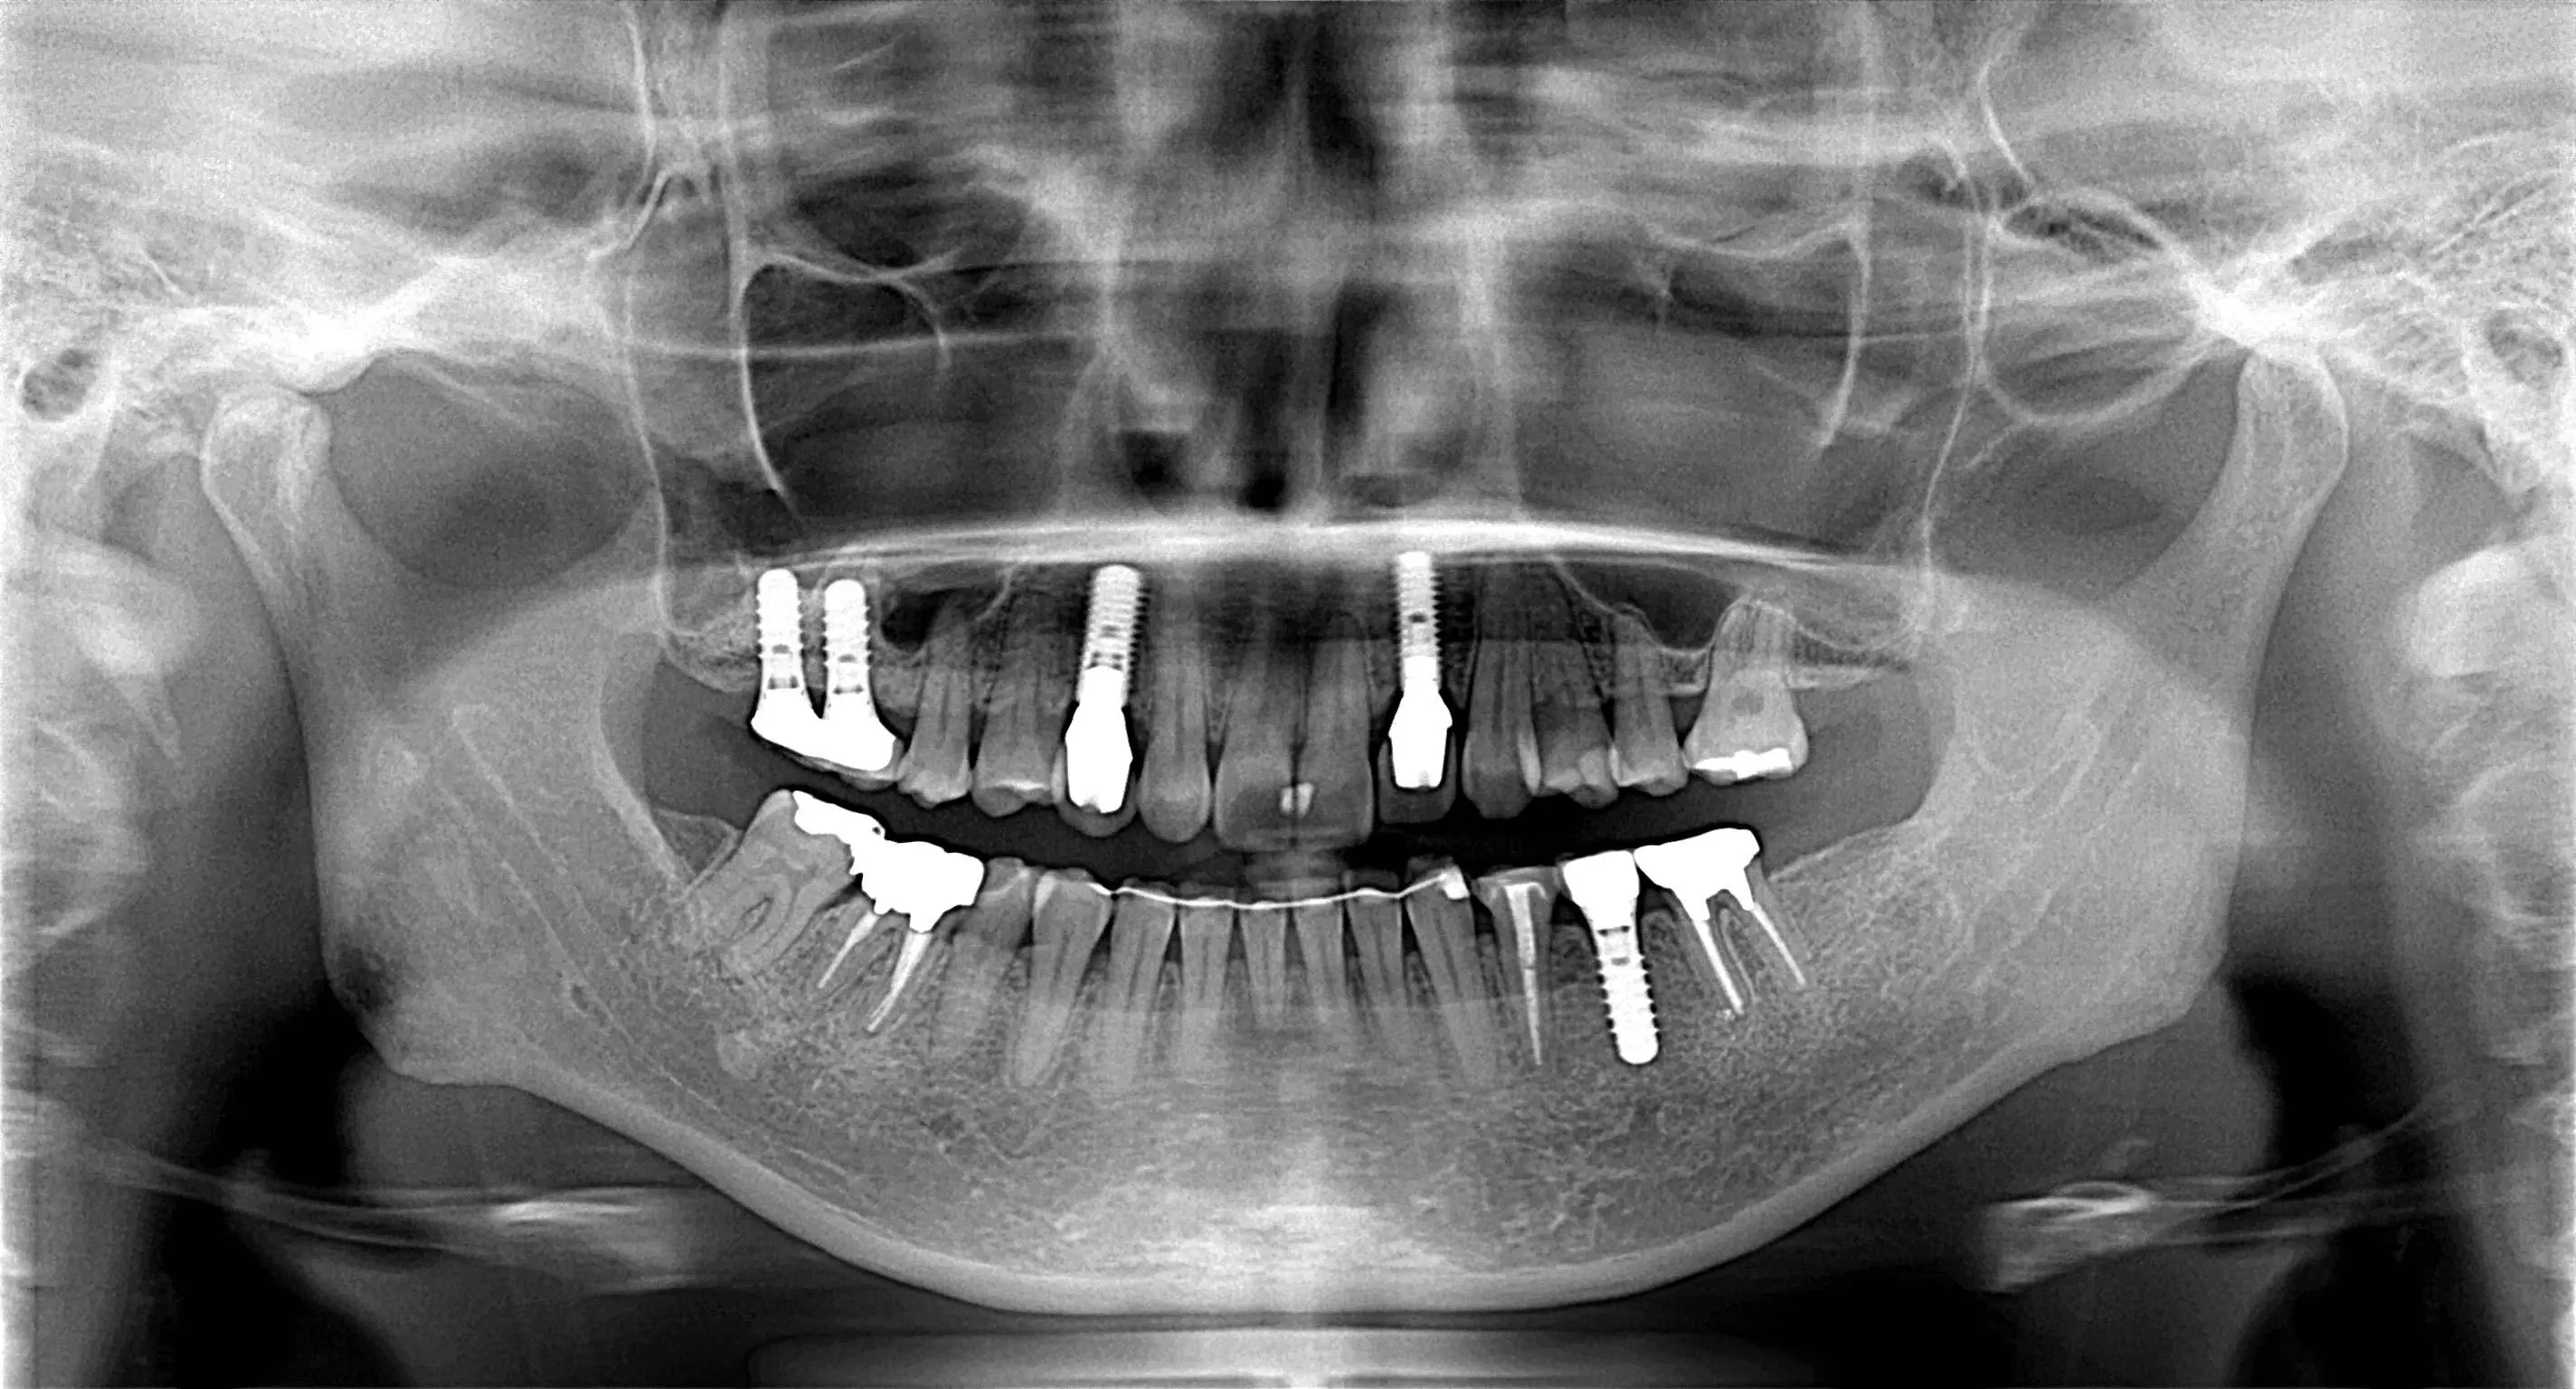

抜歯即時埋入・即時荷重

年齢 52歳 性別 男性

治療期間 4ヵ月 費用 2,800,000円

抜歯即時埋入・即時荷重 抜歯即時埋入・即時荷重